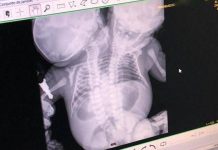

Bebê nasce dentro de quartel do Corpo de Bombeiros em Presidente Prudente

Bebê nasce dentro de ambulância durante atendimento do SAME em Presidente Prudente